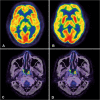

Methods: Sixty pretreatment stage I/II ENKTL patients were enrolled in this retrospective study and divided into survival (n = 45) and death (n = 15) groups according to their status at the end of follow-up. A control group consisted of 60 healthy subjects. Regional cerebral glucose metabolism was evaluated on a voxel-by-voxel basis using statistical parametric mapping (SPM8) under a certain significance level (P < 0. 001) and voxel threshold (K = 100 voxels).

Results: Decreased metabolism was noted in patients, involving the bilateral prefrontal and orbitofrontal cortex, partial parietal and occipital cortex, cingulate gyrus and cerebellum; the sensorimotor cortex was largely spared. Increased metabolism was observed in the bilateral putamen, amygdala, and parahippocampal gyrus. Compared with the survival group, the death group had higher metabolism in the bilateral amygdala, putamen, left thalamus, uncus, and parahippocampal gyrus. Only B symptoms were associated with the increased metabolism of basal ganglia and thalamus (BGT). Patients with high metabolic tumor volume, total lesion glycolysis (TLG) and BGT metabolism had a poor prognosis. TLG and maximum standardized uptake value (SUVmax) LBGT/SUVmaxRight cerebellum were associated with Eastern Cooperative Oncology Group (ECOG) and prognostic index of natural killer lymphoma and Epstein-Barr virus-DNA (PINKE) scores. In multivariate analysis, only ECOG was an independent prognostic factor of both progression-free survival (PFS) and overall survival (OS). PINKE was an independent prognostic factor of OS.

Conclusion: Pretreatment stage I/II ENKTL patients exhibited abnormal regional cerebral glucose metabolism. Higher pretreatment glucose metabolism in BGT could predict a relatively poor prognosis but did not surpass the predictive values of ECOG and PINKE in stage I/II ENKTL patients.